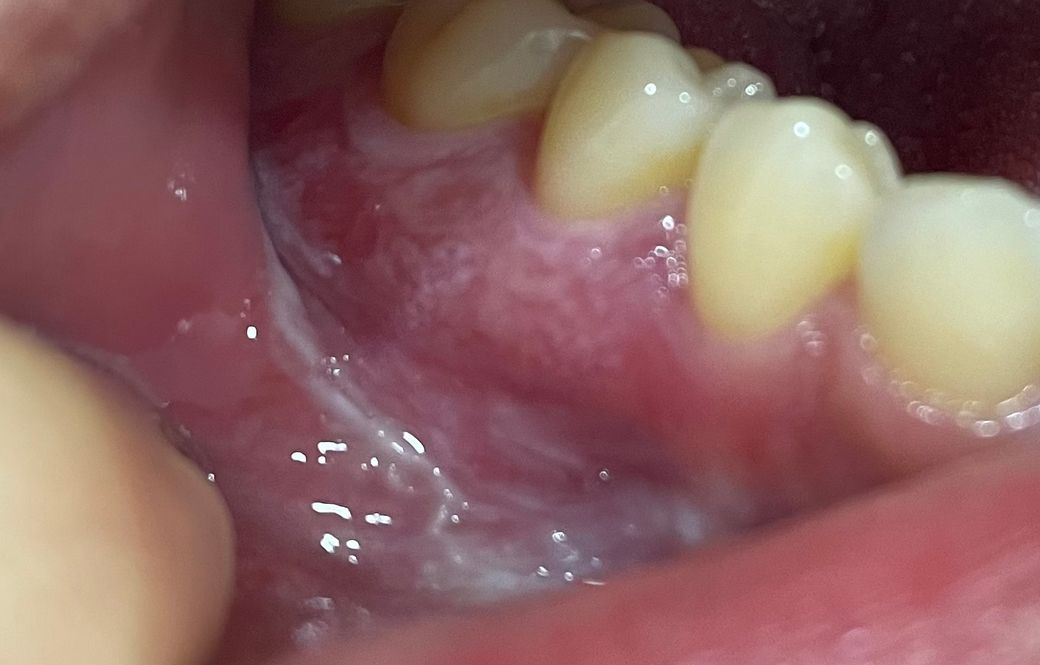

잇몸이 하얗게 되서 누르면 아파요 ㅠㅠ

모유수유중인데 어금니쪽 잇몸이 몇주전부터 하얗게 되서 뜨겁고 매운거 먹을때나 손으로 꾹 누르면 아프고 평소엔 안아파요 치과가서 스켈링은 몇일전 했습니다

• 1번 째 사진

• 안녕하세요 치과의사 김철진입니다. 사진에 보이는 부위는 뜨거운 음식을 드셔서 잇몸 표면이 화상을 입은거 같습니다. 당분간은 저부위에 자극이 가지 않도록 해주시는게 좋을것같습니다.

• 임신을 하거나 출산 이후에는 호르몬 변화에 의해서 치은염이 자주 나타날 수 있습니다. 또한 구내염도 자주 나타나며 현재와 같은 잇몸으로 인한 불편감도 자주 나타납니다. 대부분은 호르몬에 의한 영향으로 큰 문제가 되지 않으나 2주 동안 지속된다면 치과 방문 후 다른 연조직 질환이 아닌지 감별 진단을 받아보셔야 합니다.